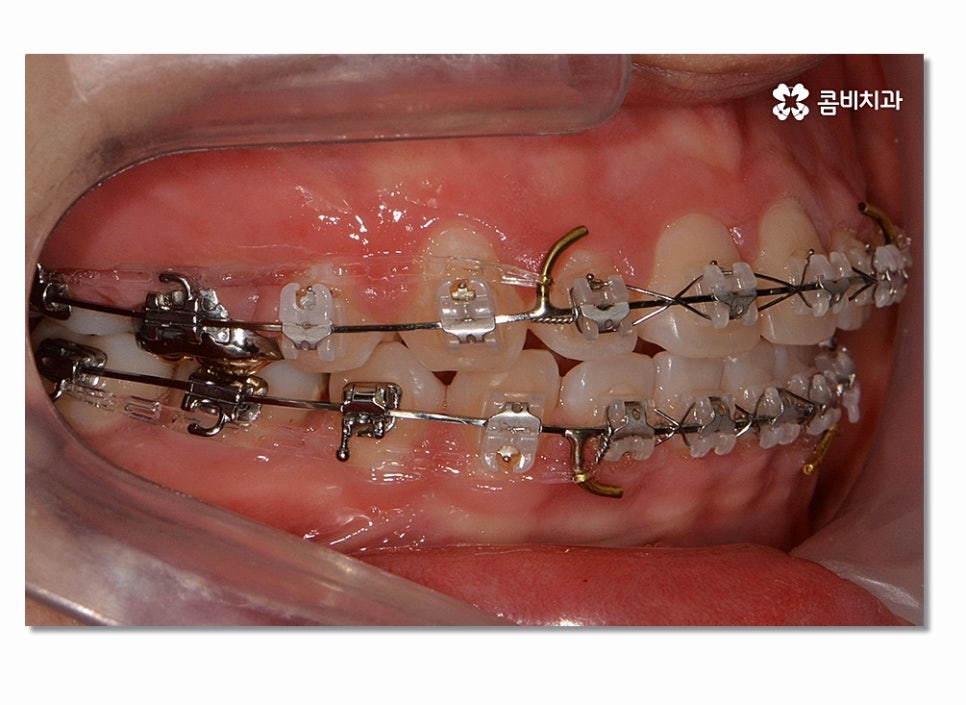

돌출입을 개선하기 위해서는 기본적으로 앞니의 각도와 배열, 위치 등의

조절이 필요하며 발치를 해야 하는 경우 보편적으로 송곳니 옆

작은 어금니를 발치하여 치아의 이동 공간을 확보하는 경우가 많다고 할 수 있어요.

돌출입치아교정이 시작되면 이처럼 전방으로 뻐드러진

앞니를 시간이 지남에 따라서 후방으로 이동시키면서 돌출입이

점점 개선되며 이러한 치열의 변화는 교합도 잘 맞물리도록

위 사진을 보시면 치아교정 과정을 통해서 치열의 가지런함은 물론이며

측면에서 보더라도 돌출입이 많이 개선된 것을 느낄 수 있을 거예요.